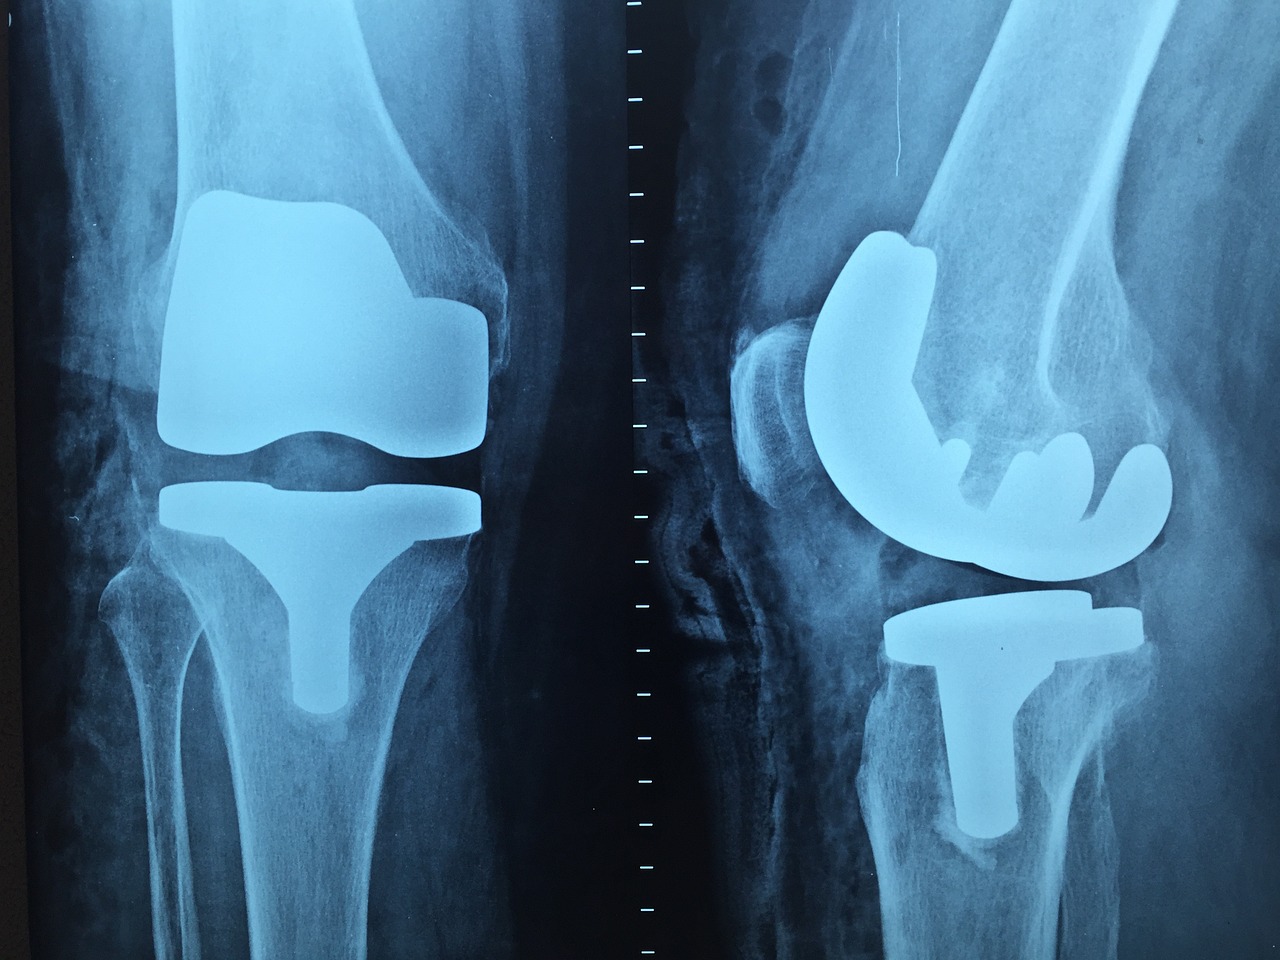

전치환술 (Total Knee Replacement, TKR)

이 수술은 무릎 관절의 모든 부분을 인공 관절로 교체하는 것을 말합니다.

반치환술 (Partial Knee Replacement, PKR)

이 수술은 무릎 관절의 일부분만 인공 관절로 교체하는 것을 말합니다.

5. 인공관절 삽입

모양내고 다듬어진 뼈에 인공 관절을 삽입하고, 필요한 경우 뼈 시멘트로 고정합니다.

인공 관절은 금속과 플라스틱의 조합으로 만들어져 있습니다.